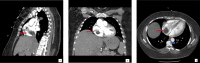

Syncope is a common emergency department (ED) chief complaint. Rarely, syncope can be the result of right ventricular outflow obstruction from an intracardiac tumor, such as an intracardiac extension of intravenous leiomyomatosis (IVL). Typically, this type of tumor is confined to the pelvic veins, but in very rare cases, it can extend through the inferior vena cava into the right atrium. Point-of-care ultrasound (POCUS) can be a crucial tool in the ED for identifying intracardiac tumors presenting as syncope and expediting clinical management. We present the case of a 39-year-old female with no prior medical history that presented to the ED having experienced dyspnea on exertion and two syncopal episodes prior to ED admission. POCUS use in the ED elucidated the presence of a right atrial mass and further imaging showed a mass on the patient's uterus. After surgical removal of a portion of the atrial mass, a subsequent biopsy revealed it had leiomyoma-like features; as such, the patient was diagnosed with IVL. This case illustrates the importance of using POCUS in the ED to help determine the etiology of syncope. Although intracardiac extensions of IVL are rare, it is important for emergency physicians to keep this diagnosis in the differential in patients with symptoms or risk factors suggestive of IVL with intracardiac extension.